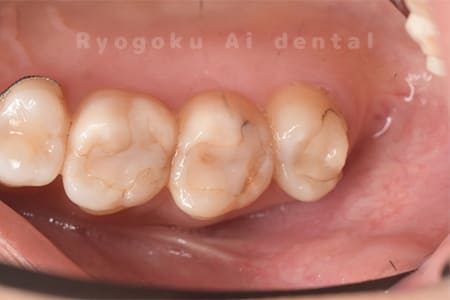

Case08

-

- 原因

- 虫歯

- 治療内容

- セラミックインレー

- 治療費用

- 77,000円

奥歯の黒い点が気になるということで来院された患者さんです。白い詰め物を外したところ、虫歯が中で大きく広がっていたため、患者さんと相談し、セラミックインレーで治療を行いました。

<リスク・副作用>

過度の咬合や衝撃で割れることがあります。